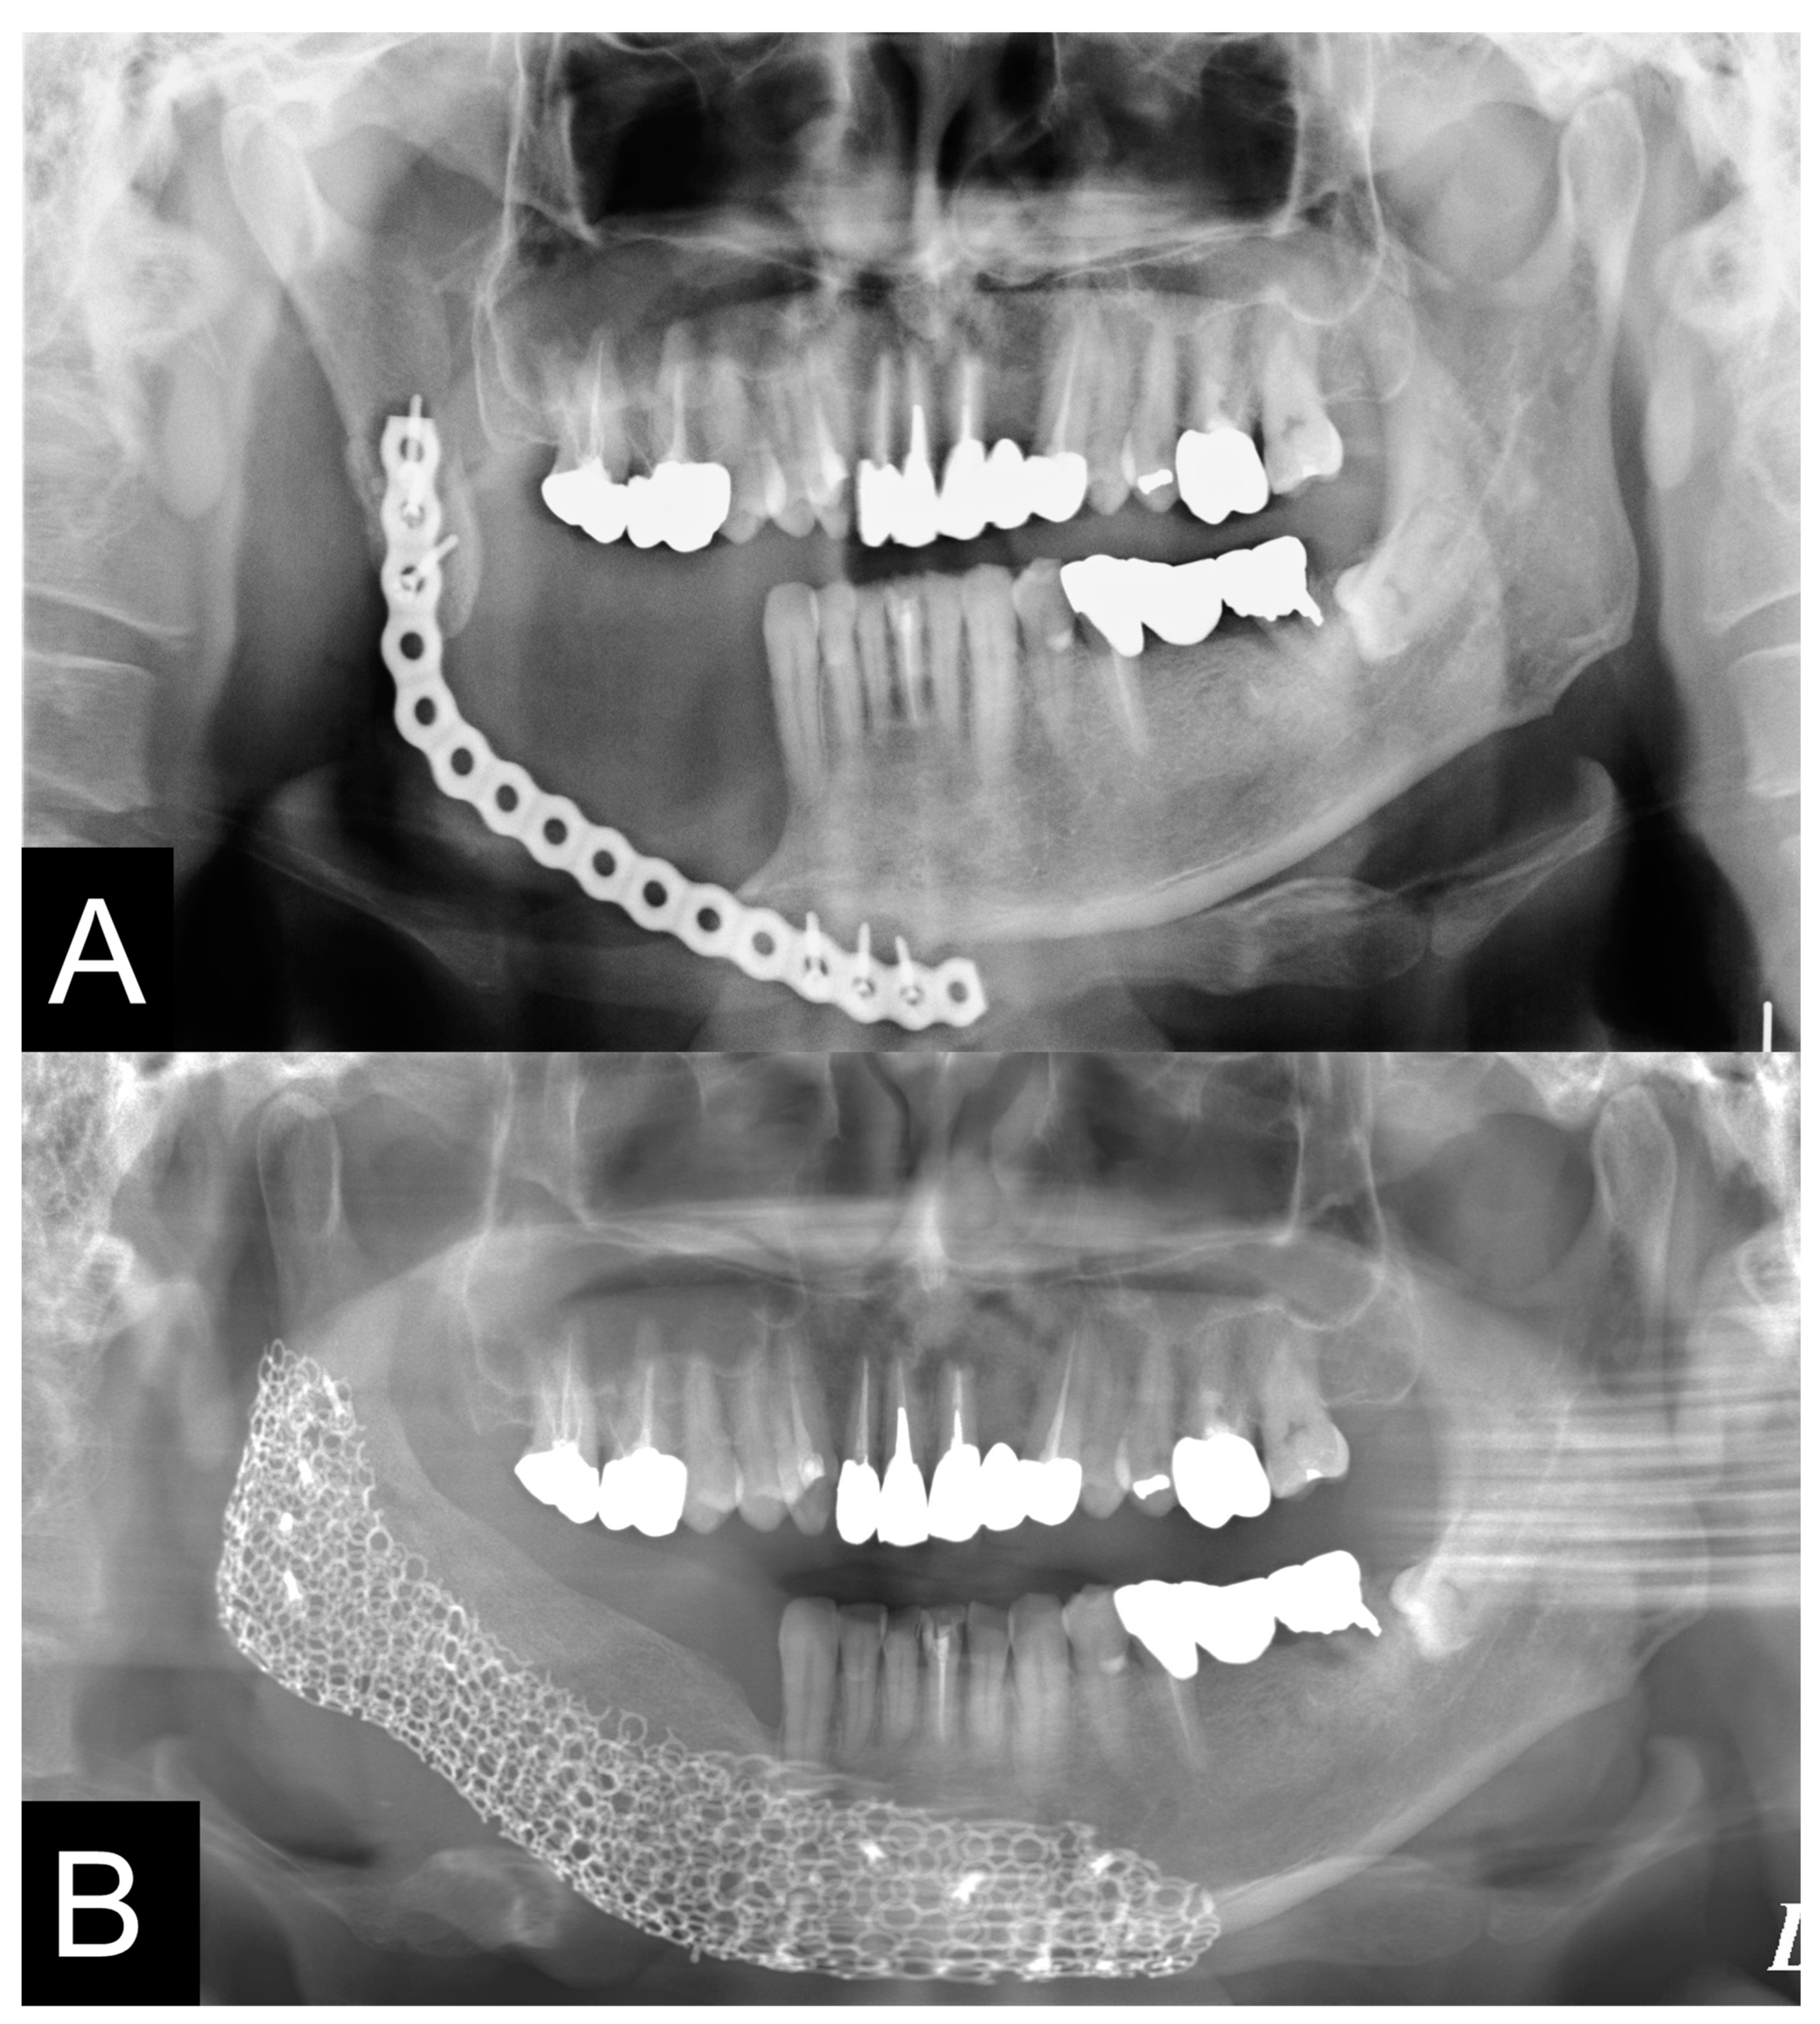

2.9. Evaluation of Mandible

3.3. Evaluation of Reconstructed Mandible